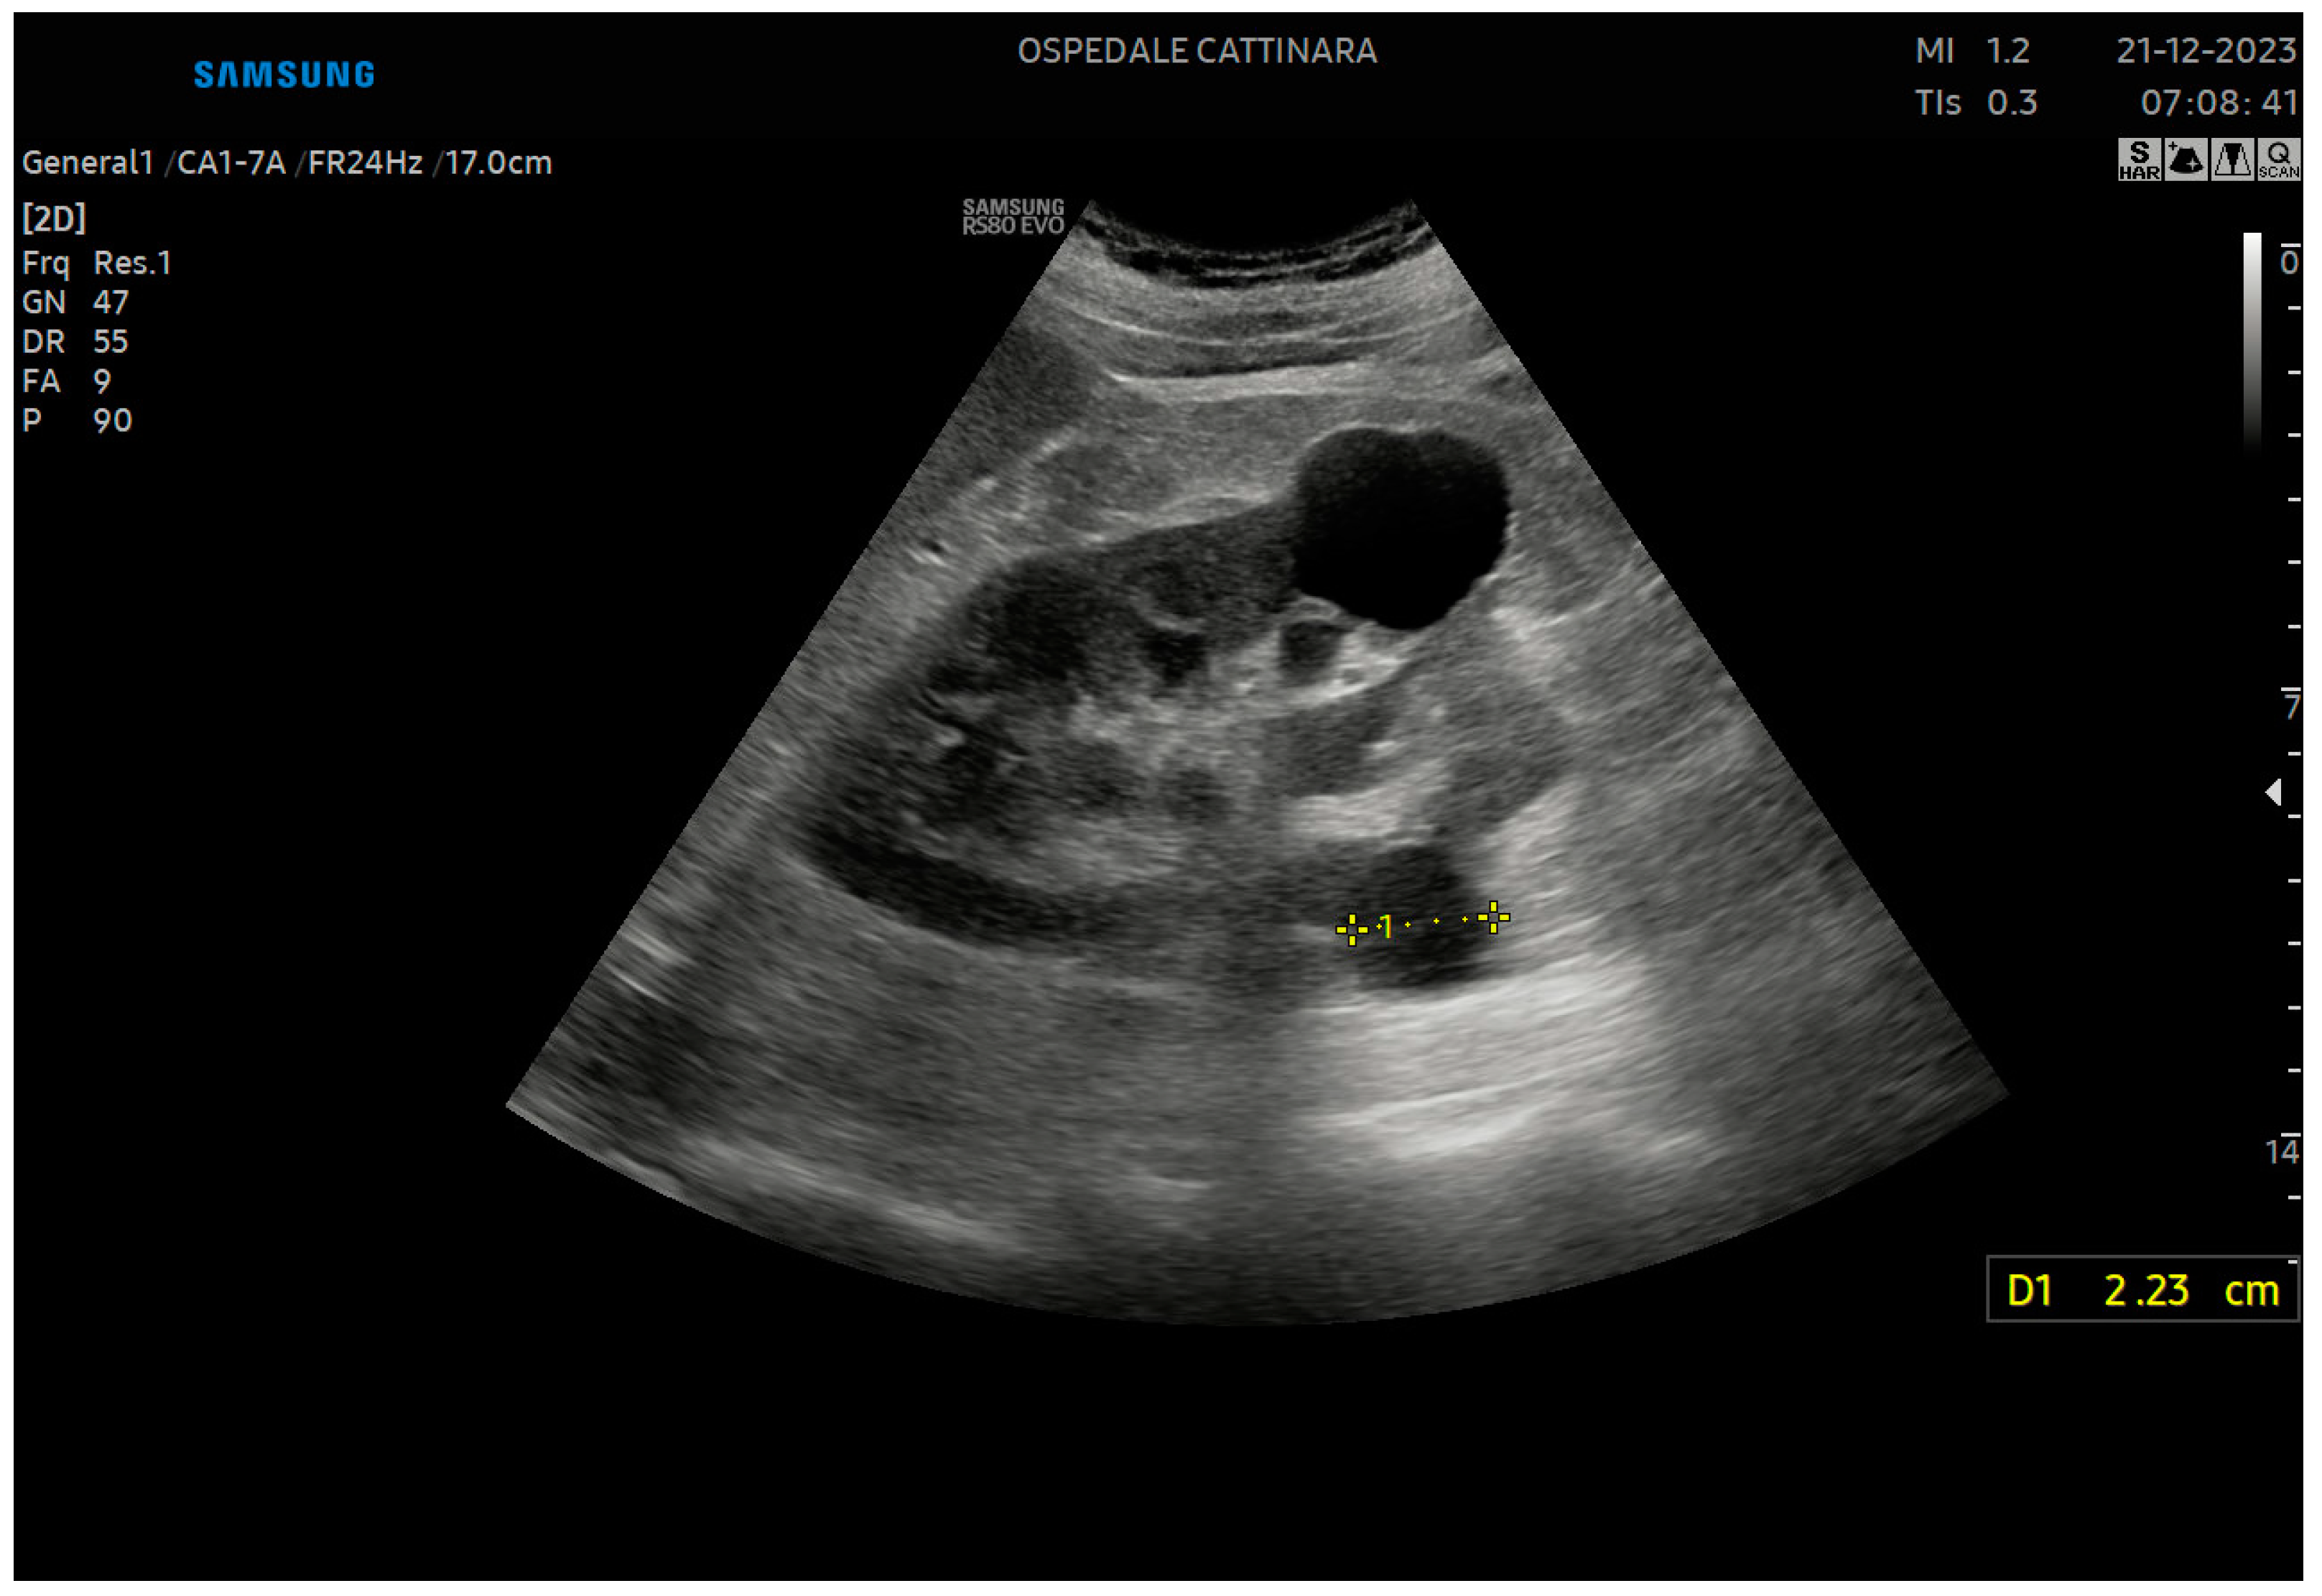

3.8. Ureteropelvic Junction Obstruction

3.9. Acute Renal Infection